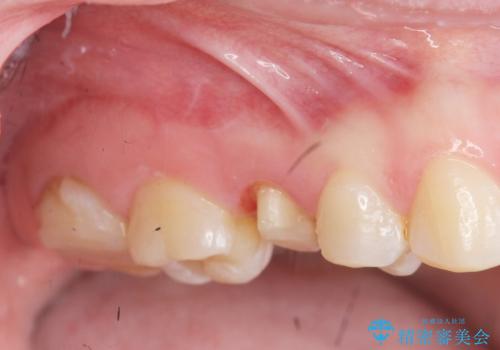

放置した虫歯を外科を行い抜歯を回避

- 放置していた虫歯が欠け、いよいよ怖くなり治療を希望され来院されました。

歯ぐきよりも深い虫歯 →歯周外科による歯周環境の整備

を適宜行うことで良好な結果を得ることができます。

症状に応じて適切な処置を行ったことで、抜歯を回避し良好な結果を得ることができました。